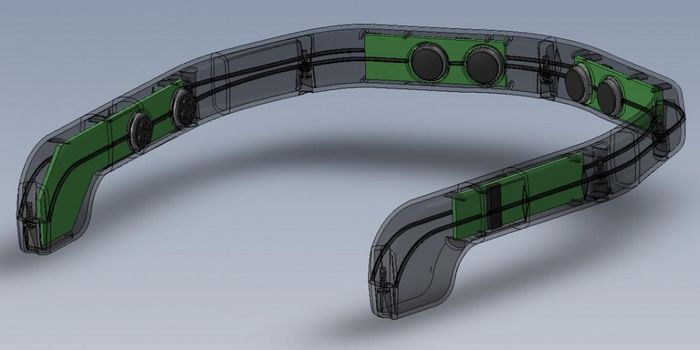

SEP 16, 2021Clinical & Molecular DXForget uncomfortable chest straps or clunky wristbands—thanks to a new innovation in nanotechnology, your t-shirt ...